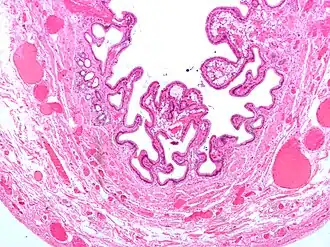

| Micrografia da vesícula biliar com colecistite e colesterolose. | |

A colecistite crónica resulta da inflamação continua de baixo grau da vesícula, ou de vários ataques autolimitados de colecistite aguda. Microscopicamente o infiltrado inflamatório é constituido por macrófagos, que ingerem as membranas celulares das células destruídas, apresentando-se cheios de lípidos: macrófagos xantelesmizados. Além disso são visíveis seios de Rokitansky-Aschoff: ou evaginações na membrana devido a menor taxa de renovação da mucosa que de destruição. Por vezes à calcificação da mucosa, denominada de vesícula de porcelana: nestes casos o risco de cancro da vesícula é muito mais alto.